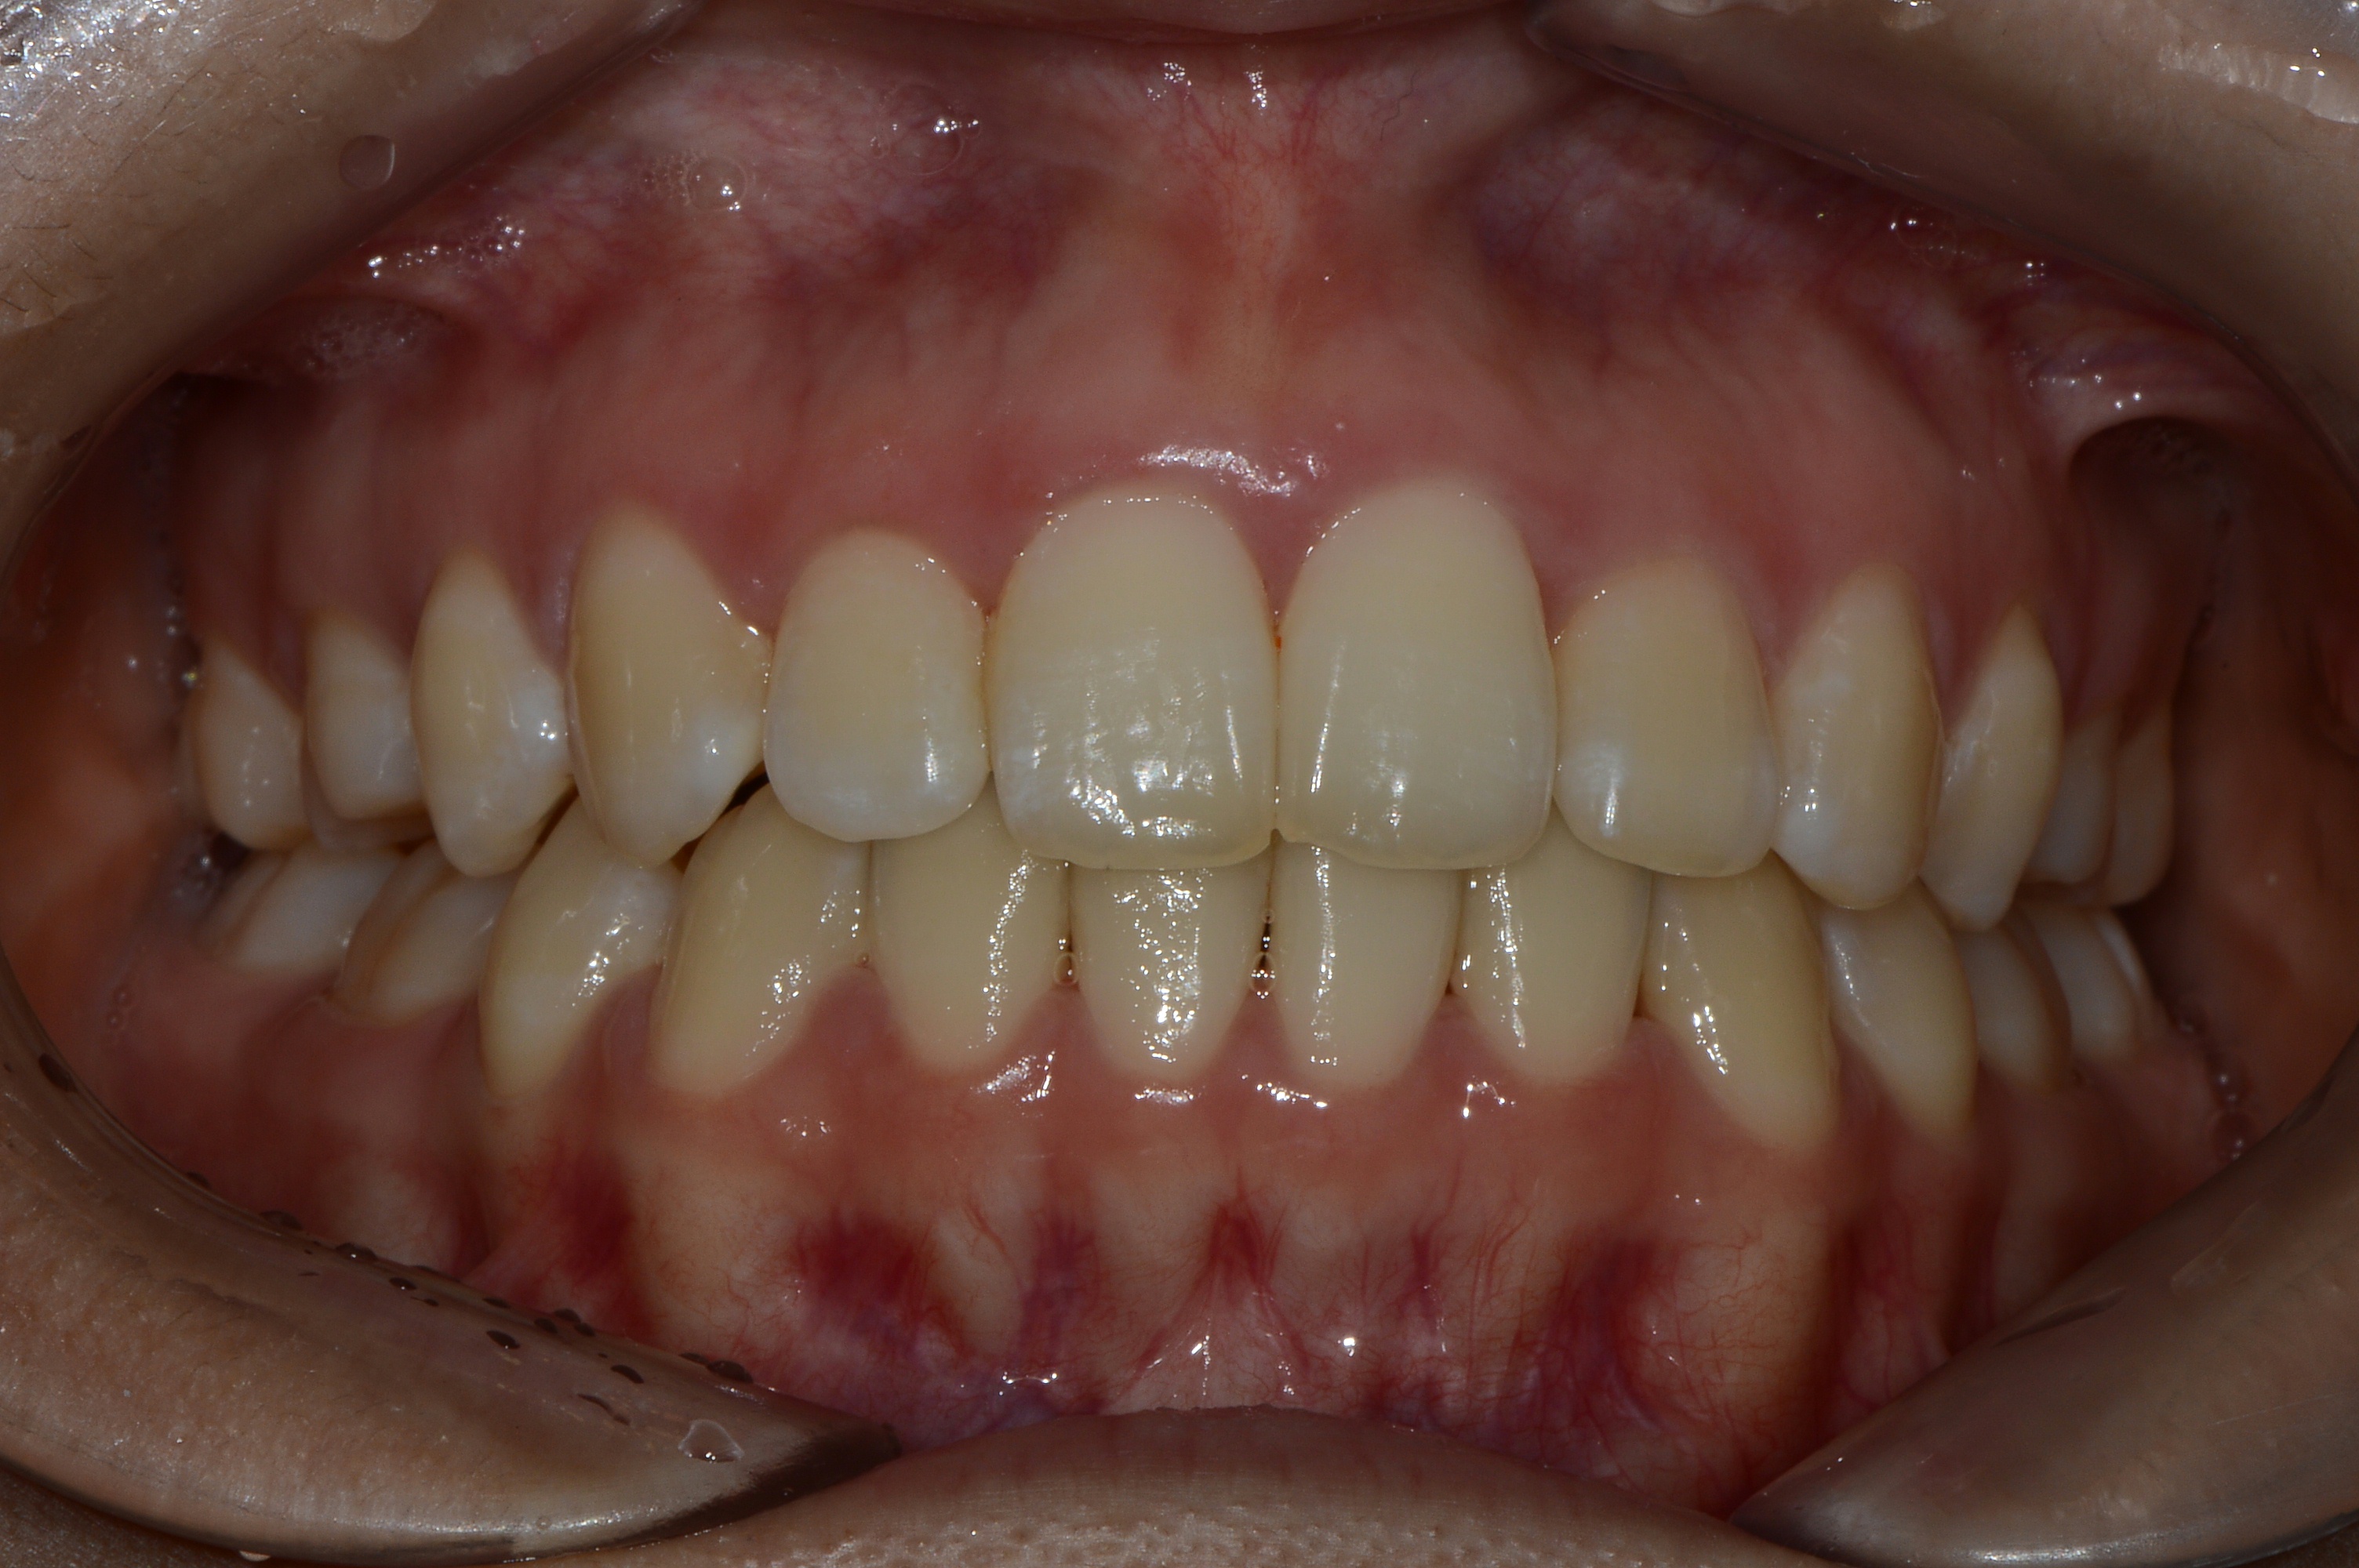

치료 후 사진입니다.